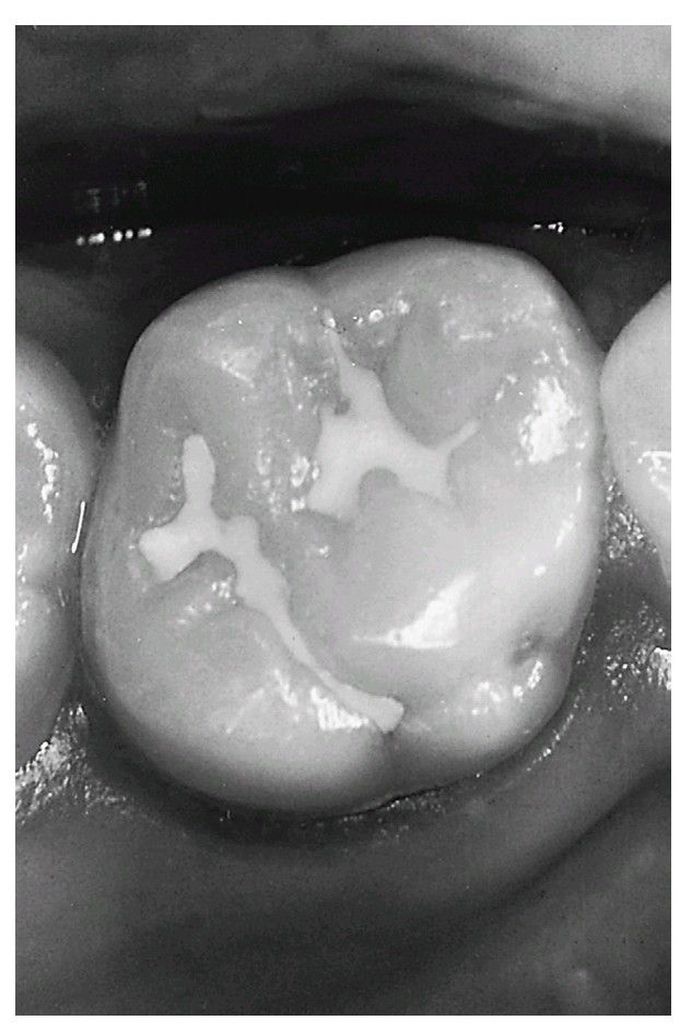

Fissure sealant

Maxillary molar tooth with opaque sealant that has been in place for 5 years.